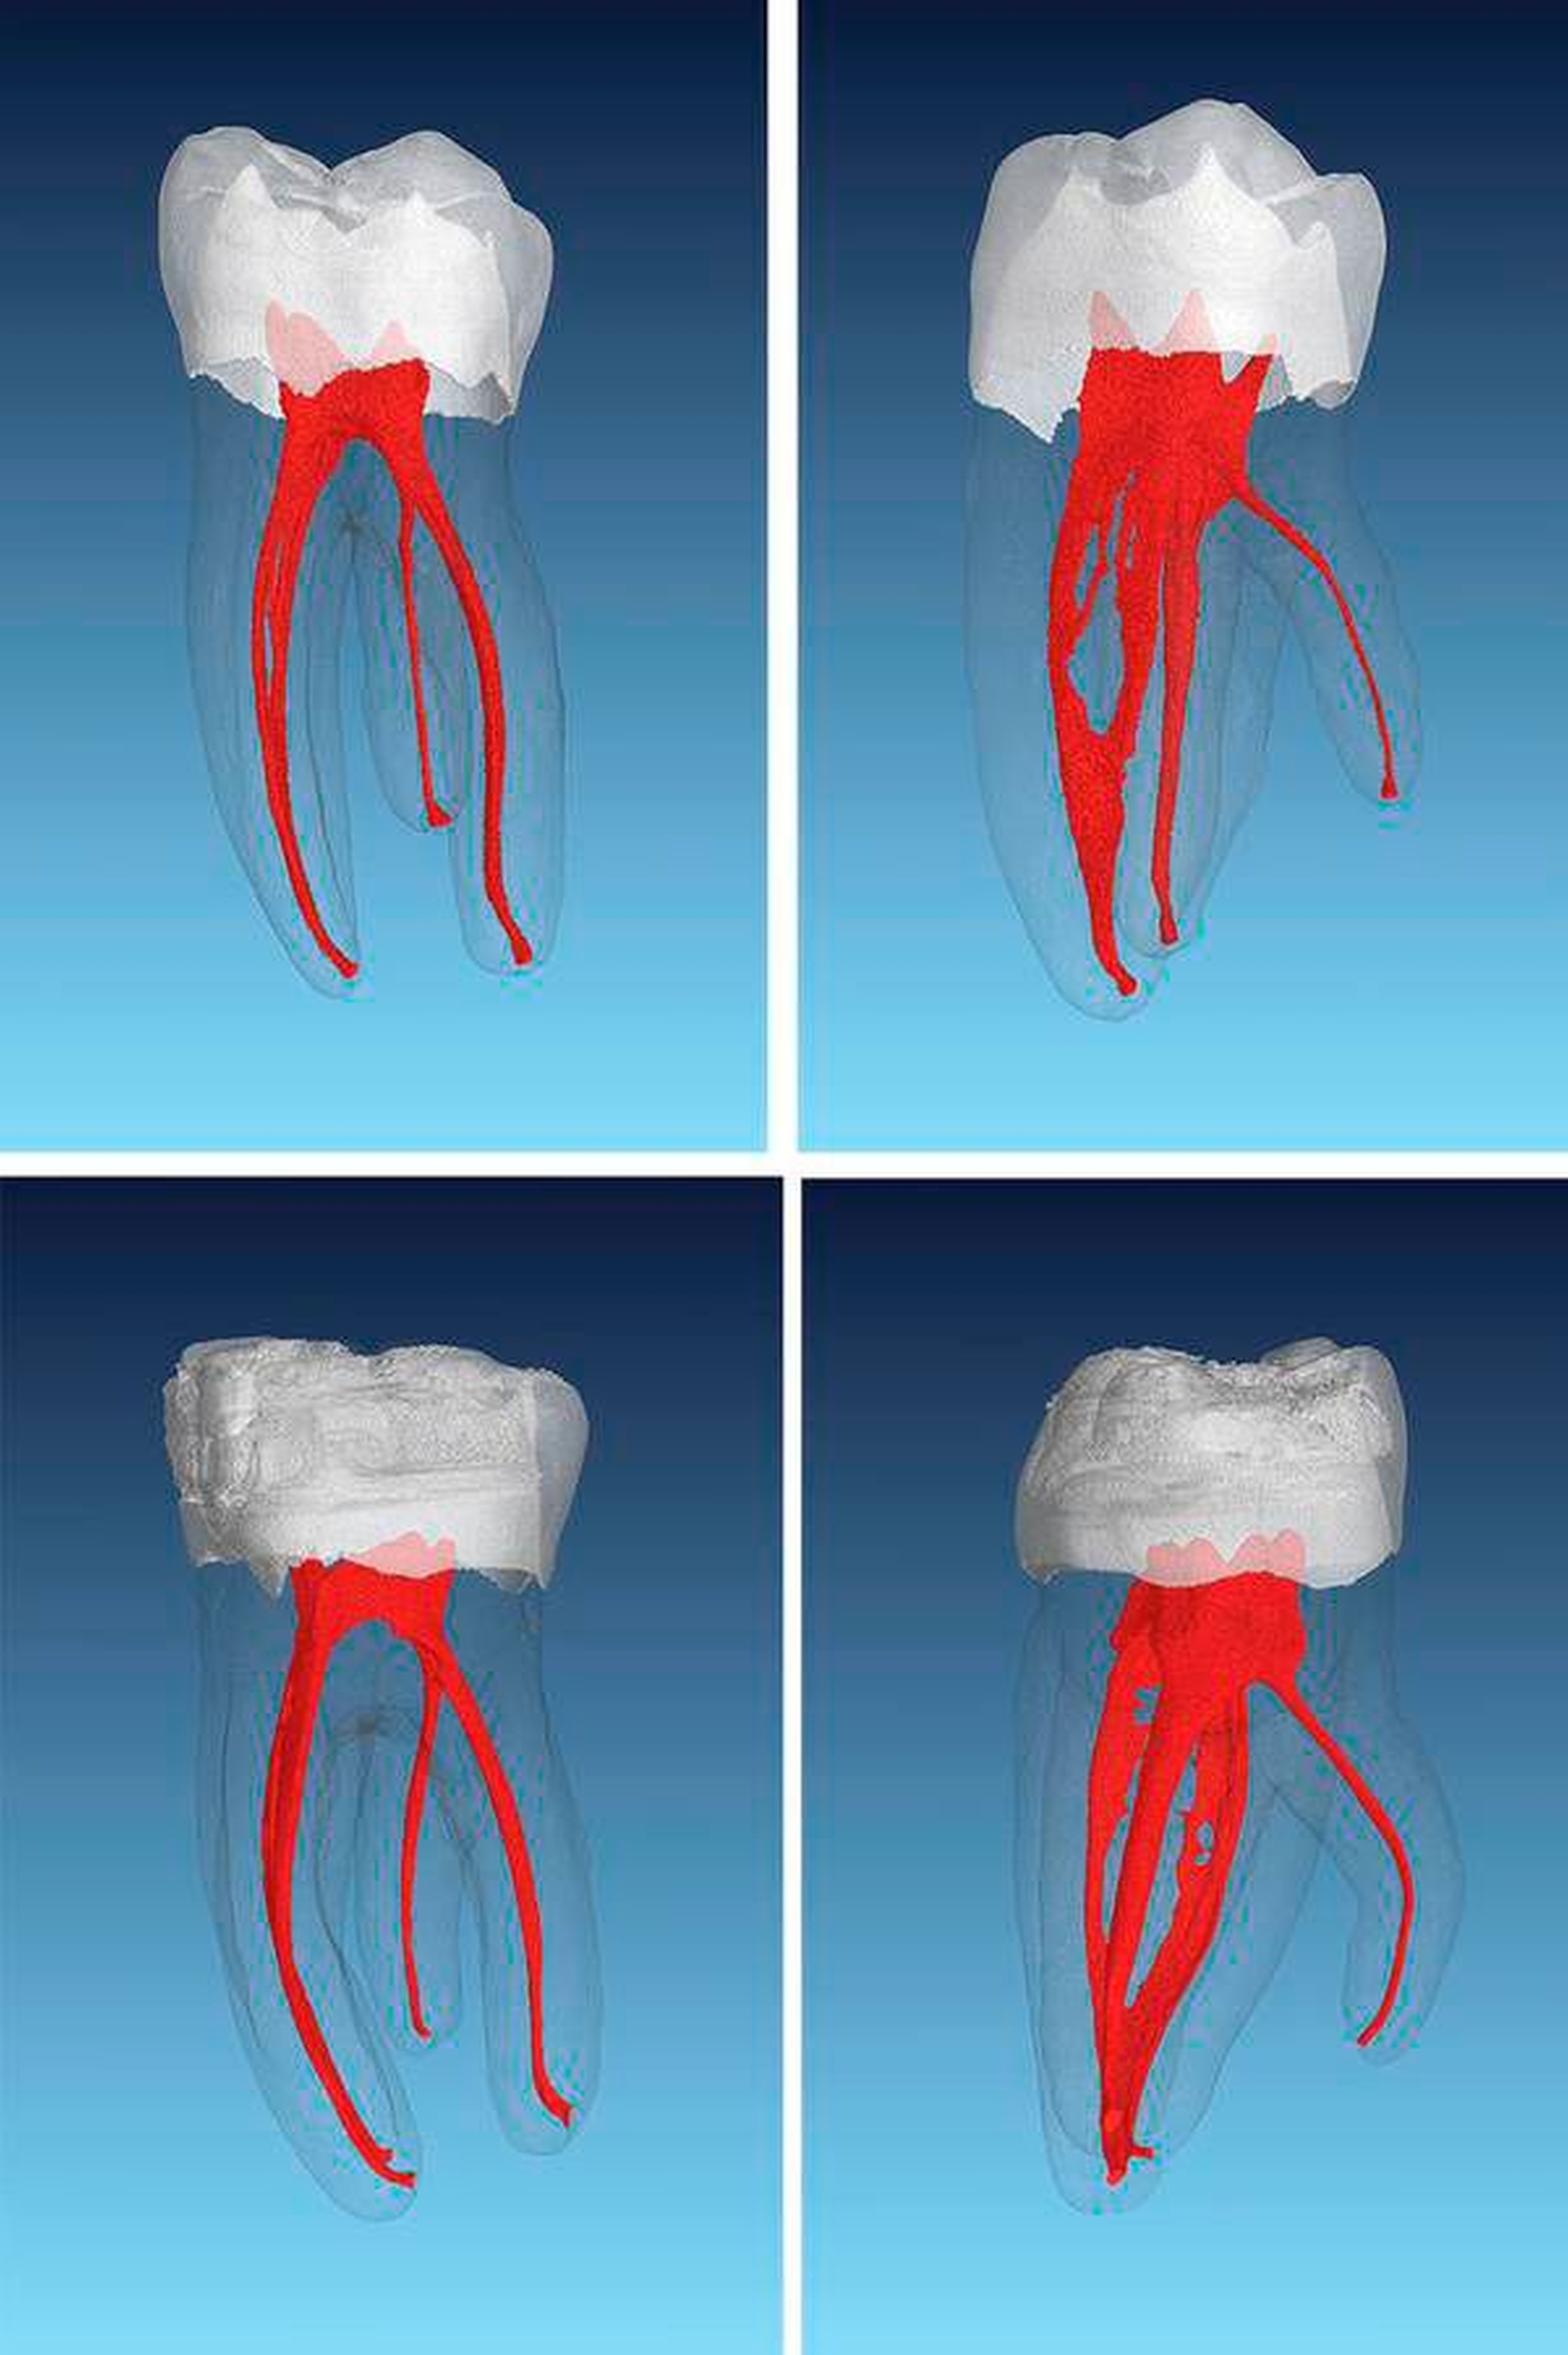

In den meisten Fällen sind Unterkiefer-Molaren zweiwurzelig. In einigen Fällen gibt es jedoch spezifische Variationen wie verwachsene Wurzeln, zusätzliche Wurzeln und völlig unterschiedliche Formen wie die c-förmigen Wurzelkanalsysteme (Abbildung 1). Viele kleine, akzessorische Kanäle tragen zusätzlich zur Komplexität bei [Vertucci et al., 2006].

Während der Zahnentwicklung wird die äußere Form der Wurzel durch die primäre Dentinapposition bestimmt. Diese Form des Wurzelquerschnitts kann bereits Hinweise auf die innere Kanalform geben: So weisen eher runde Wurzelquerschnitte auch eher runde Kanäle im Inneren auf. Im Unterkiefer häufig anzutreffende länglich ovale oder nierenförmige Wurzelquerschnitte beherbergen oftmals zwei oder mehr Wurzelkanäle (Abbildung 2). Während die äußere Wurzelform die innere Form bestimmt, trägt die sekundäre Apposition von Dentin zur zunehmenden Komplexität innerhalb des Kanalsystems bei. Diese tritt hauptsächlich nach dem Durchbruch des Zahnes in die Mundhöhle und dem apikalen Verschluss ein [Peiris et al., 2008]. Die spezielle Komplexität der inneren Wurzelkanalanatomien nimmt daher nach Ausbildung der Wurzel über mehrere Jahrzehnte hinweg zu. Bei weiterer Zunahme der sekundären Dentinapposition werden dann aber mehr und mehr Hohlräume wie beispielsweise kleinere Verzweigungen wieder verschlossen. Es konnte gezeigt werden, dass die Komplexität der Wurzelkanalsysteme in den ersten und in den zweiten Unterkiefer-Molaren bei 30- bis 40-Jährigen am höchsten war [Peiris et al., 2008].